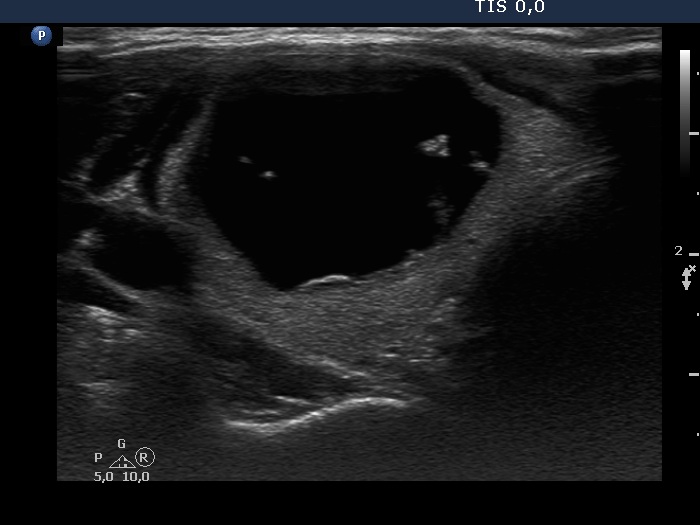

Ultrasonography. The thyroid was echonormal. The right lobe had a cystic nodule with echonormal solid components. The subtype of the cyst is difficult to define, this is probably a peripheral-type cyst.